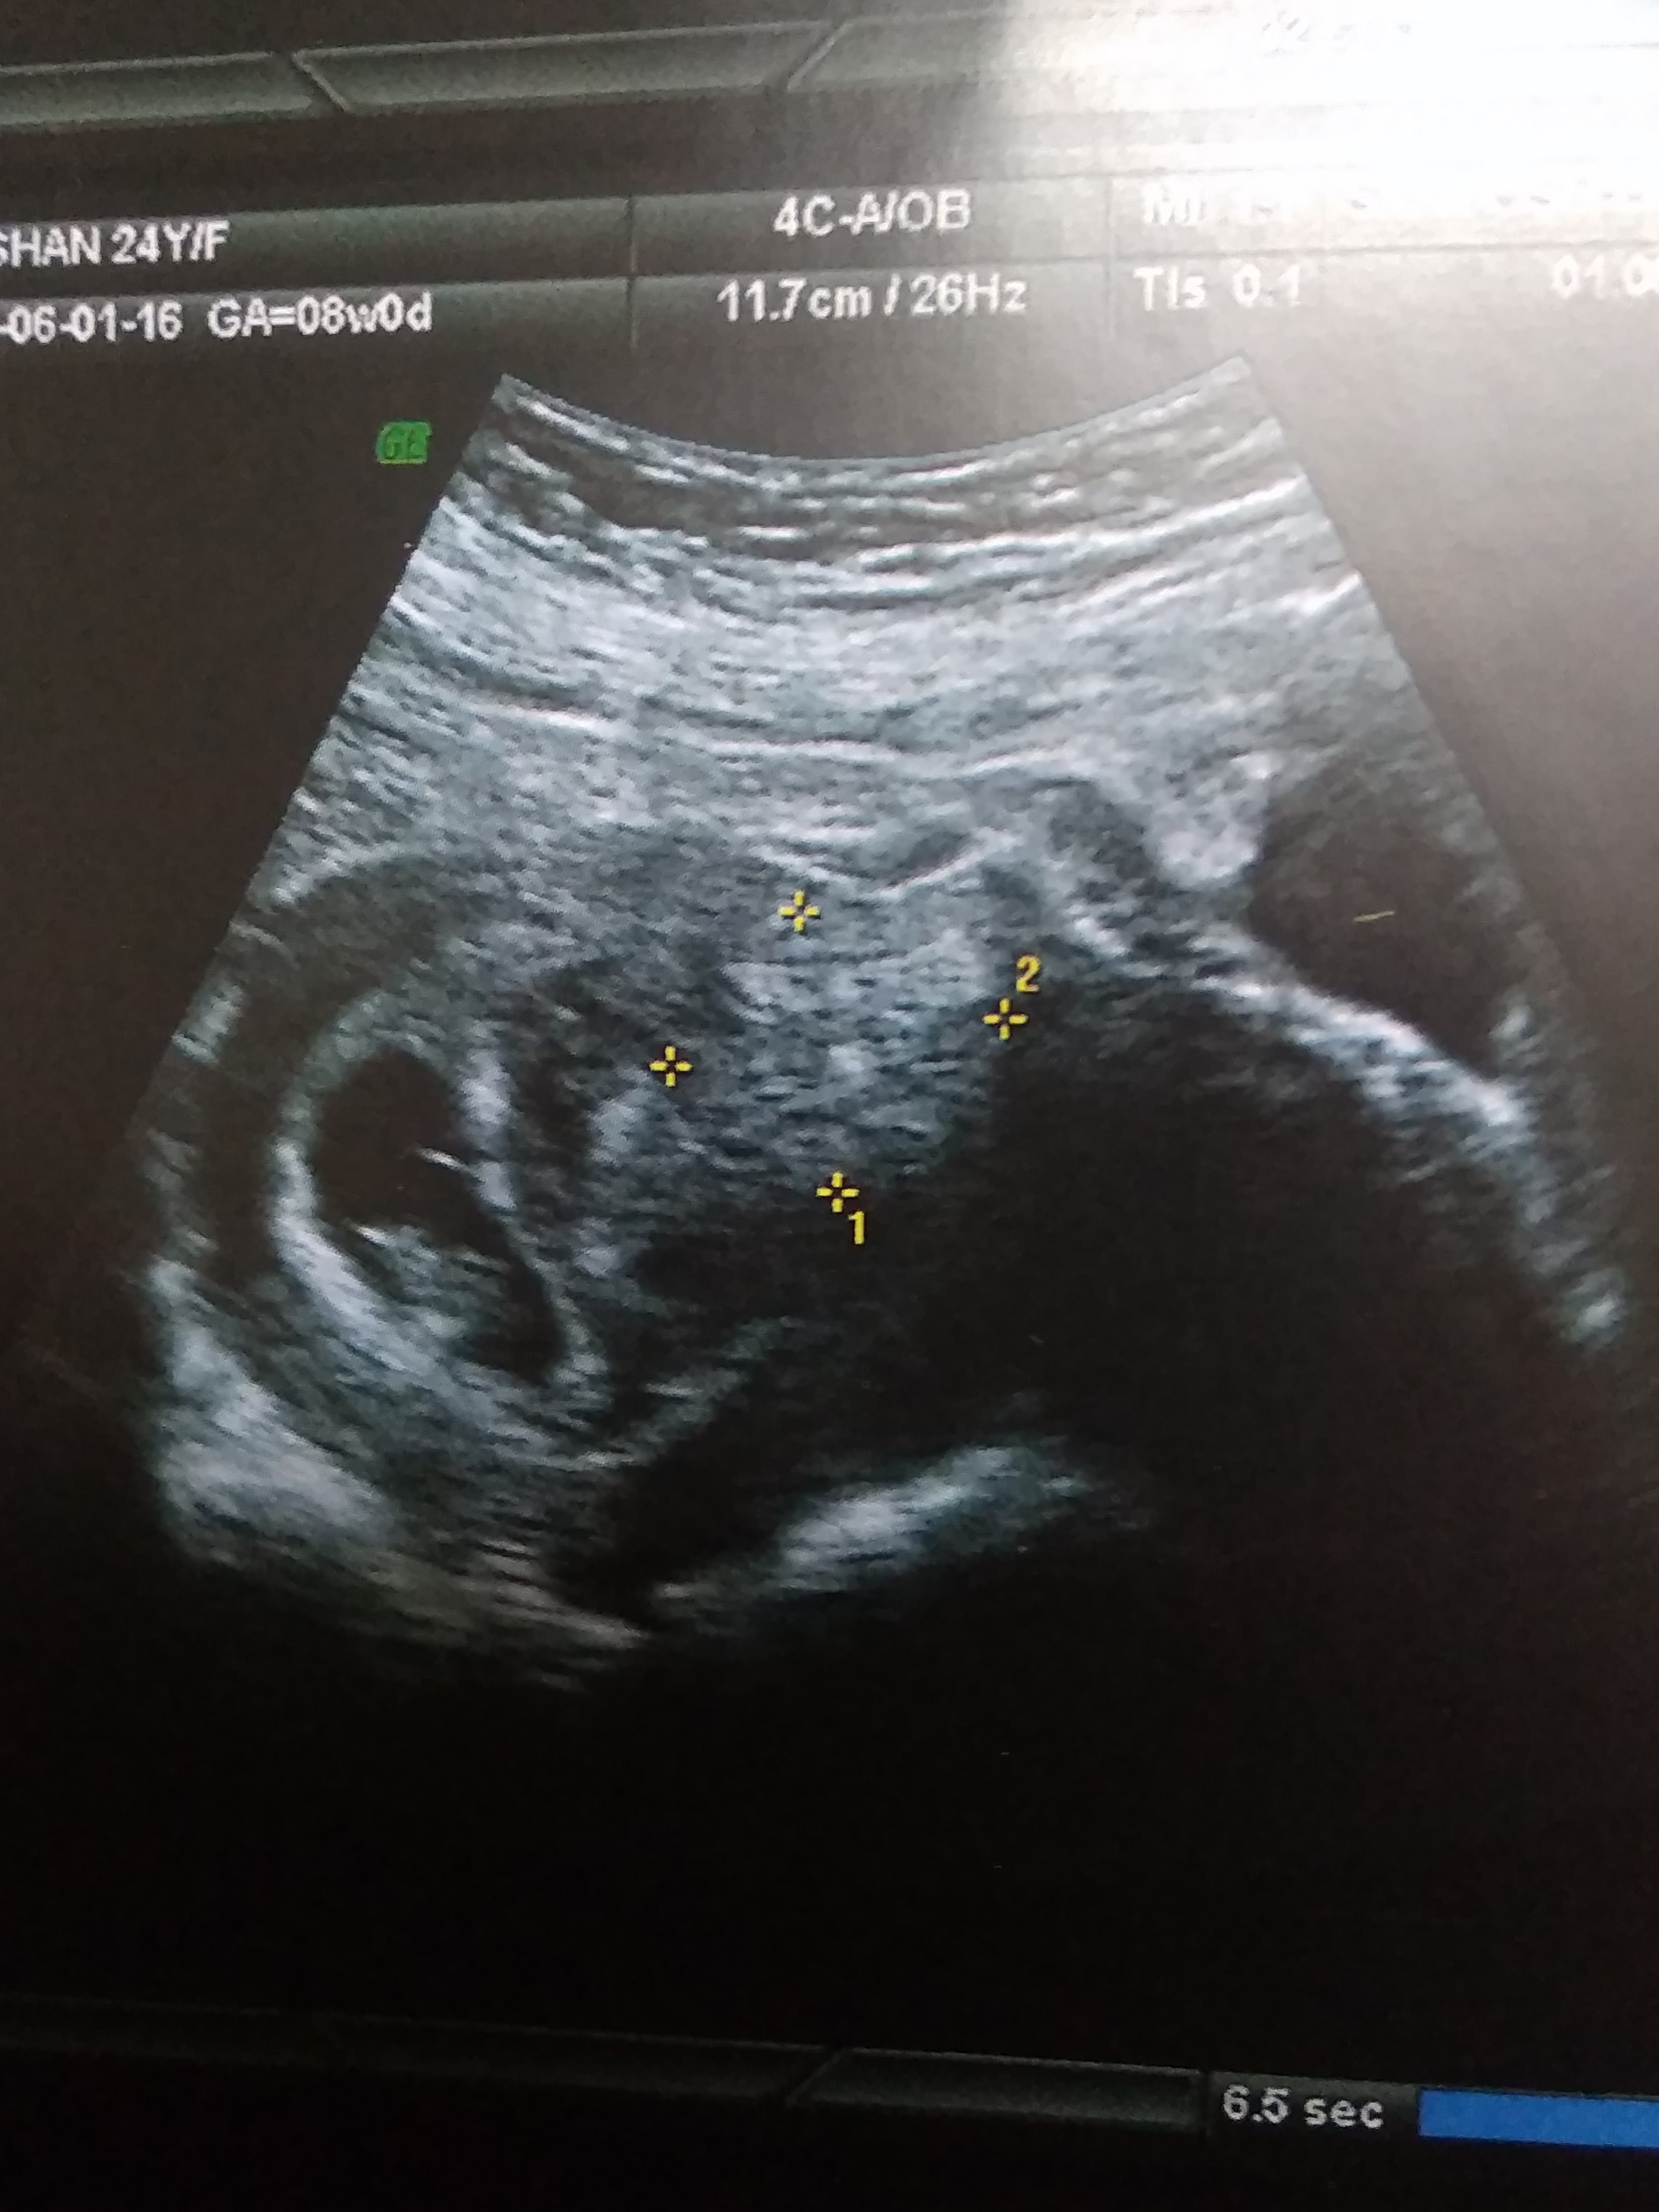

This is a abdominal scan taken at 8weeks. Any guesses, boy or girl??

I thought ramzi will be good from 6-8 weeks. Just for fun!